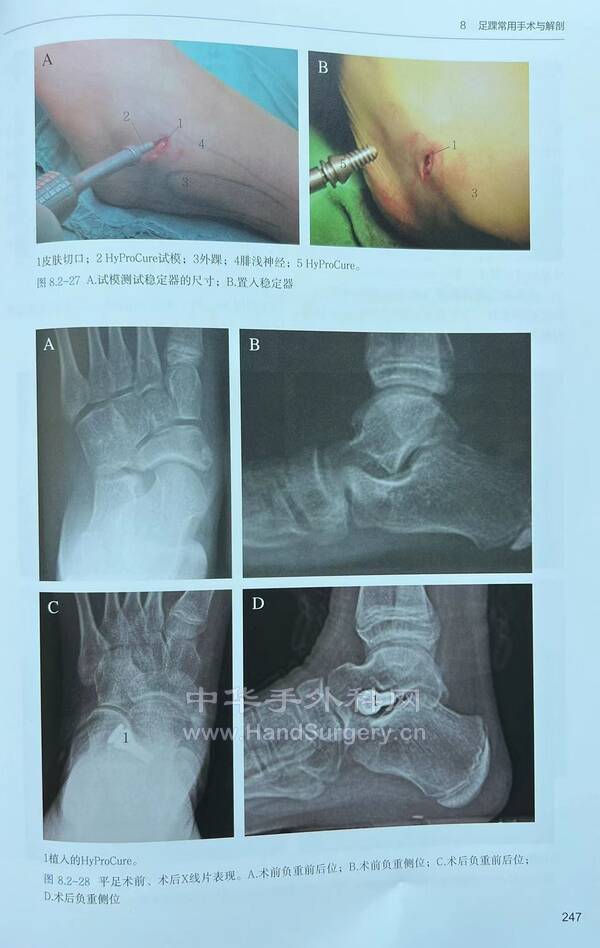

今日得偿所愿,上午跟着老师参观双侧青少年柔韧性扁平足微创扁平足制动器矫正术,双侧副舟骨切除胫后肌腱止点重建术的

13岁男性患者,用的威高扁平足制动器(但大博2代扁平足制动器相对较好)。

副舟骨切除,用直径3.0mm可吸收螺钉固定,与胫后肌腱加固缝合,腱骨缝合,用2.5mm克氏针在舟骨上打孔,放入强生直径3.0mm可吸收铆钉(丝线亦为50%可吸收线),远端与胫后肌腱编织缝合加固!术后6周不能行走。